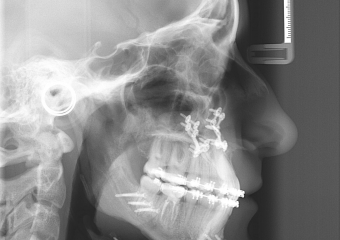

Telerradiografia perfil após a cirurgia  - Clínica Cliniface

Telerradiografia perfil após a cirurgia